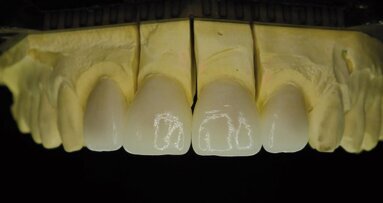

Afin de réaliser une prothèse idéale, l’utilisation d’un guide implantaire est fortement indiquée, en particulier lorsque l’édentement atteint ...